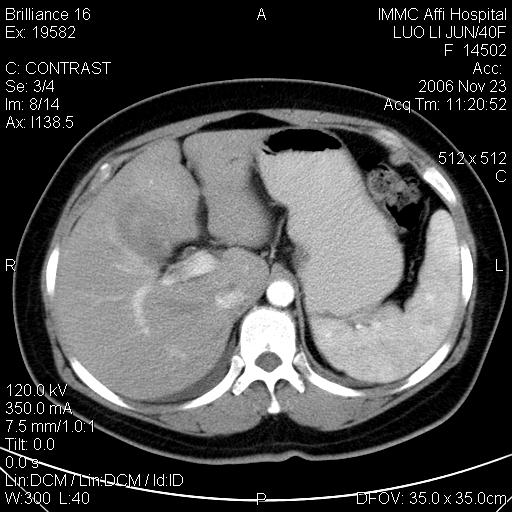

标题: CT5664:我也发一个肝脏的片子大家看看

很典型的肝癌。

速升速降,典型肝癌.

支持-----考虑肝癌----[-从片上看增强早期应该是动脉晚期即门脉早期]

是啊,典型的早出早归!

快进快出典型肝癌.

符合肝癌的增强特征。支持肝癌!

病灶好圆!可能恶性度不高。

不能除外肝细胞腺瘤吧,还是得结合病史。

很好的片子,可惜增强做的比较失败,a期时间没有把我好,实际到了静脉早期了,否则会更典型。

最终考虑是肝腺瘤